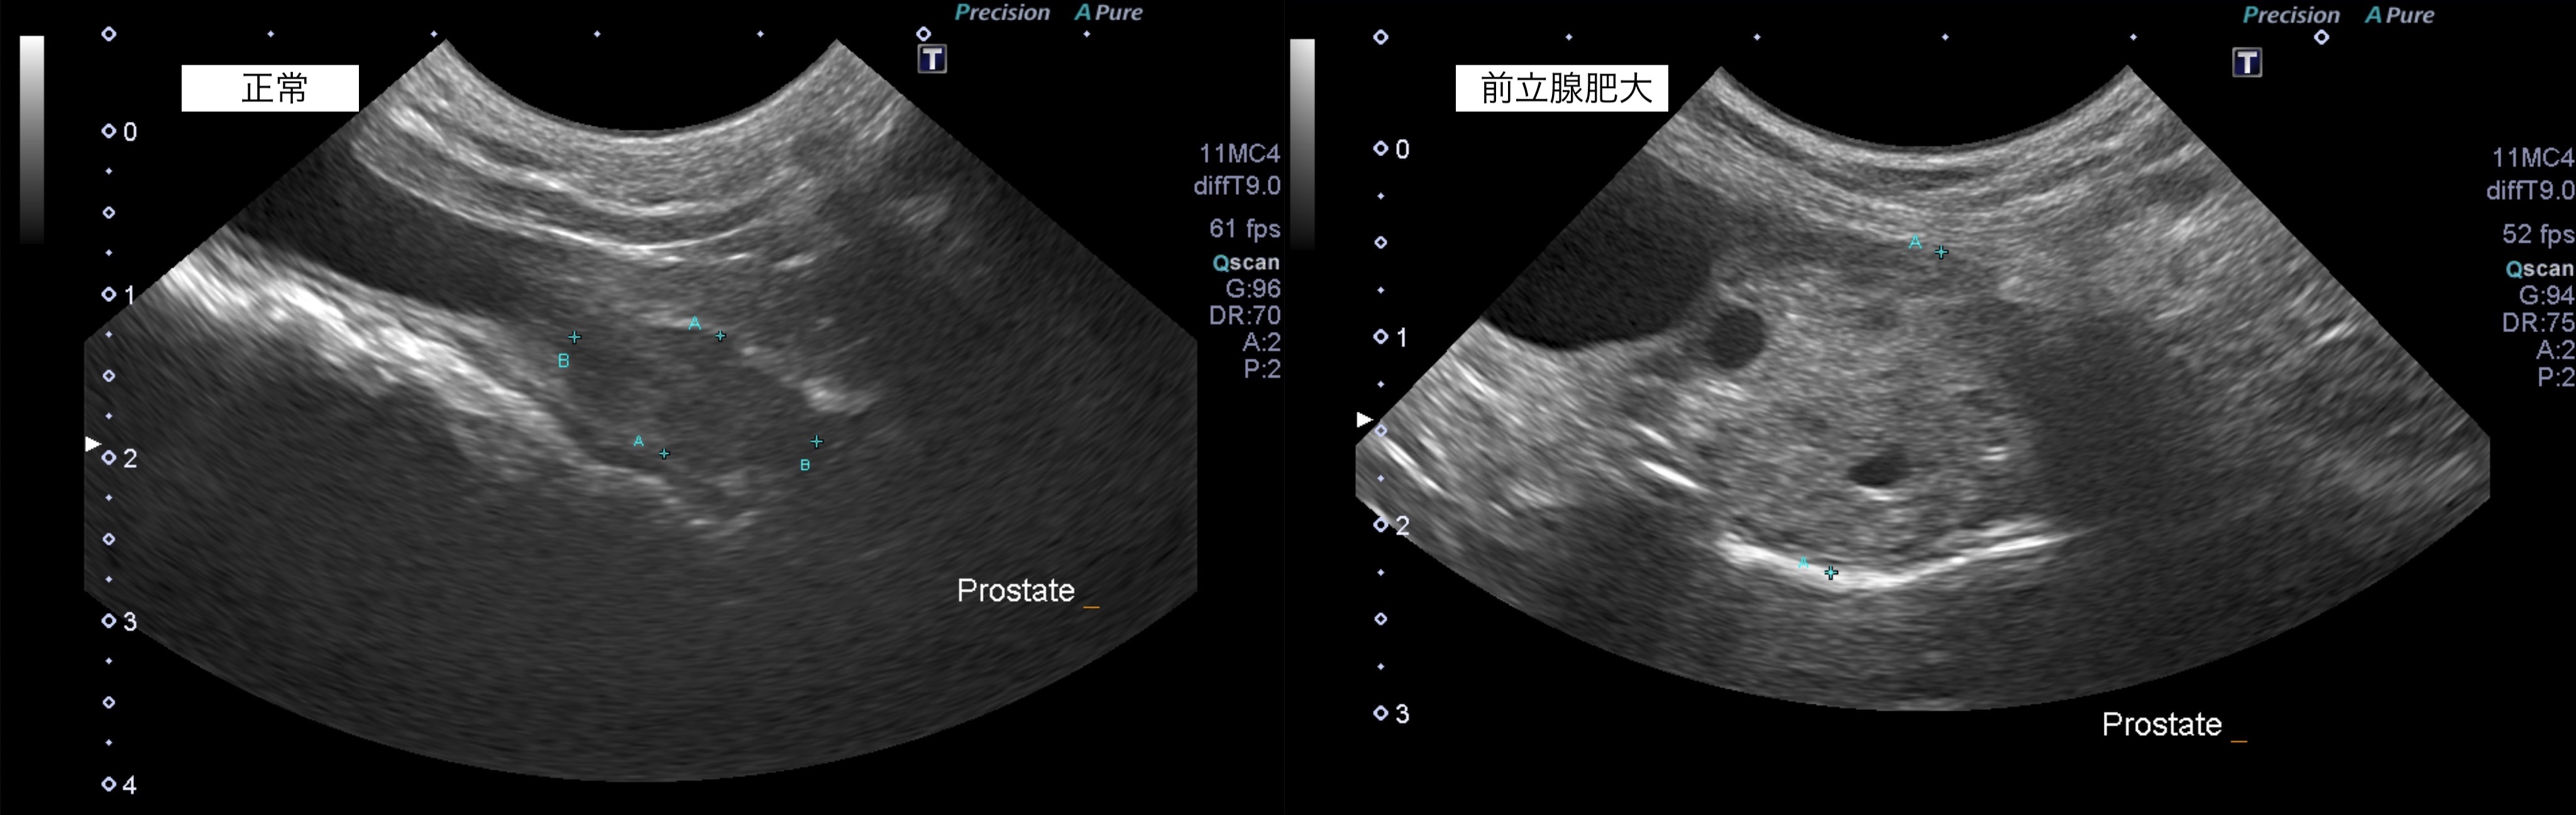

良性の前立腺肥大の犬の1例(前立腺、便秘、頻尿、去勢手術)

犬の良性前立腺肥大は、前立腺が骨盤て直腸を圧迫し、接している尿道を狭窄することで、

〈便秘〉〈頻尿〉の症状が認められます。

本症例は、便秘や頻尿などの症状がなく、定期検査で偶発的に前立腺肥大が認められました。